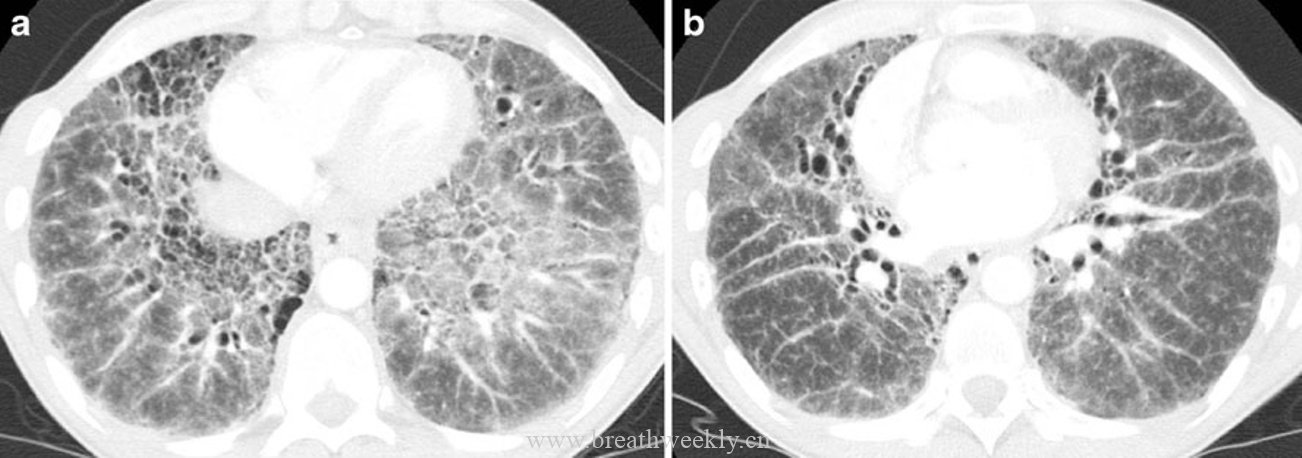

病例3:寻常型间质性肺炎(UIP)

临床资料:80岁男性,快速进展性呼吸困难。

影像表现:CT显示散在分布的铺路石征,伴牵引性支气管扩张。

病理对照:间质增厚,程度不一,部分肺泡隔正常,部分明显增厚,可见蜂窝肺。

病例4:非特异性间质性肺炎(NSIP)

临床资料:56岁女性,进行性呼吸困难。

影像表现:CT显示双肺周边为主的铺路石征。

病理对照:均匀的间质纤维化增厚伴炎症,肺泡隔内可见巨噬细胞。

UIP的CT特征包括胸膜下网状影和蜂窝肺,从肺尖到肺底逐渐加重。磨玻璃影在UIP中不明显或缺如。组织学标志是时间和空间上不均一的实质纤维化。

NSIP的HRCT主要表现为胸膜下、斑片状磨玻璃影。组织学上,均匀的间质炎症对应弥漫磨玻璃影,间质纤维化对应叠加的线状影。